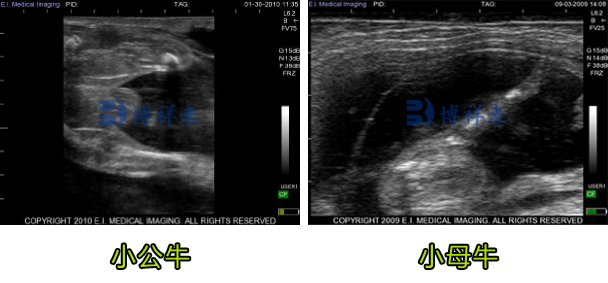

小公牛和小母牛生殖器结节在屏幕上均显示为双叶白色结构,其回声性与骨组织相似。 在小公牛中,生殖器肿胀(GS)和泌尿生殖皱襞(GF)是高回声结构。

B超测小牛公母超声图像